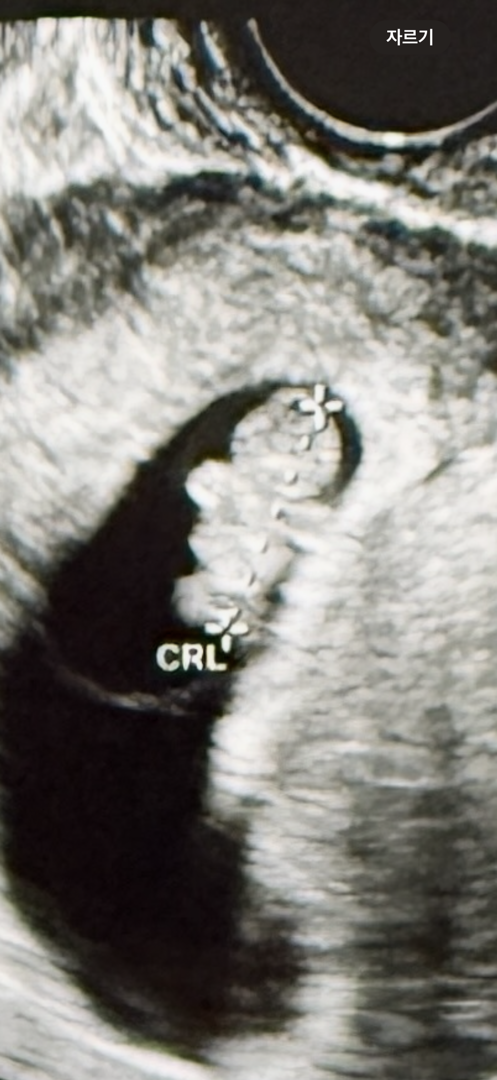

8주4일차 초음파

이전에 10주 차에 유산 수술했을 때 아기가 8주 차에 심장이 멎은 것 같다고 했었어요. 이번 임신에 6주 차인데 의사선생님이 사이즈가 작다고 하셔서, 검진받고 오늘까지 아기가 괜찮을까 걱정에 맘 놓고 임신 기뻐하지 못하다가 갈색 피가 살짝 보여서 더 불안해진 마음에 초음파 보러 오늘 다녀왔어요. 처음으로 본 제법 사람 모양 같아진 우리 아기 사이즈도 잘 맞게 큰 거 같아고 해서 다행이다 하며 좀 울었어요 ㅎ 저도 드디어 젤리 곰 봤어요! 2주 뒤에 정기검진인데 그땐 더 사람 같아질 거라고 하셔서 기대도 또 걱정도 할 거지만 그래도 오늘은 좋은 날이니 기뻐하려고요! 입덧으로 고생하지만 그래도 행복해서 글 남깁니다!